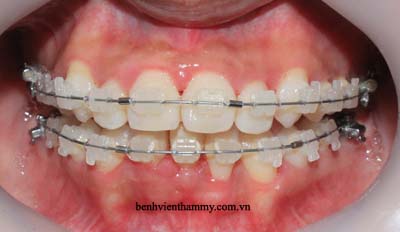

Trường hợp bệnh nhân người lớn - Răng mọc chen chúc niềng răng không nhổ răng:

(Niềng răng với mắc cài sứ thẩm mỹ)

(Thực hiện bởi bác sĩ chuyên khoa cấp I chỉnh hình răng hàm mặt-Phạm Việt Hùng-nha khoa thẩm mỹ AVA)